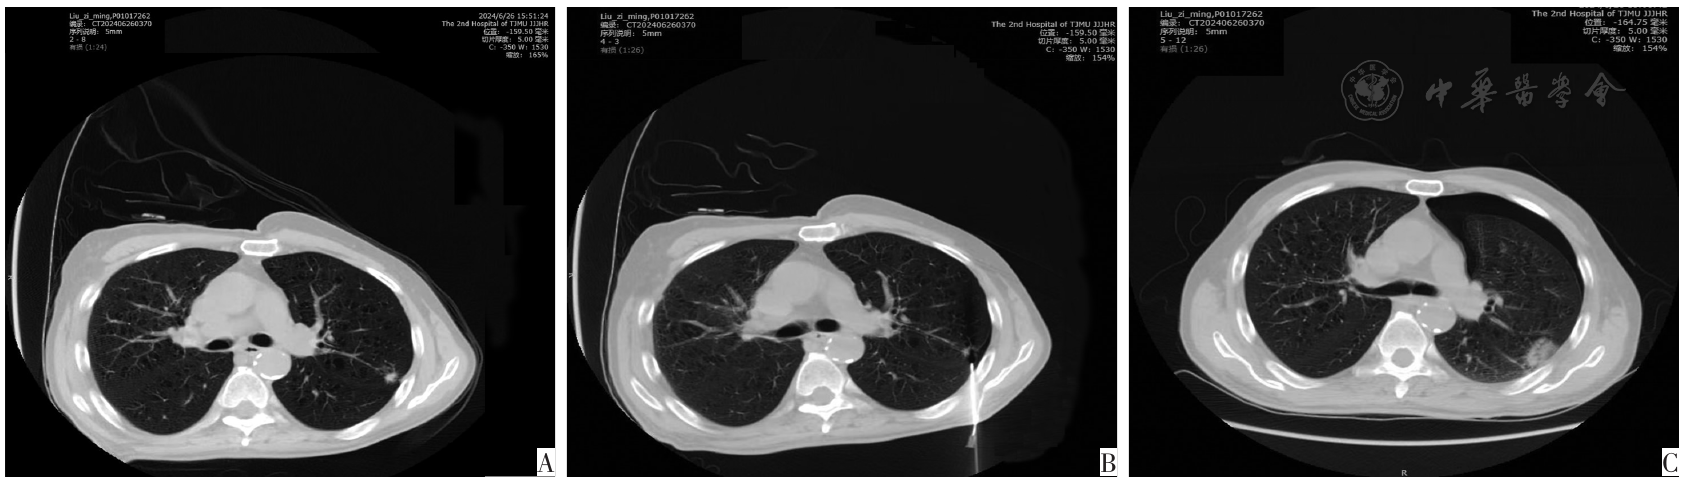

图1 CT-LNB前后69岁,男性左上叶肺结节患者CT图。图A为活检前轴向平面CT示直径9.9 mm、接触胸膜长度5.7 mm结节;图B为活检过程中获得侧卧CT示结节和经肺途径插入的活检针,肺内路径距离为17.3 mm;图C为活检后4 h仰卧CT示左侧气胸,需放置胸管